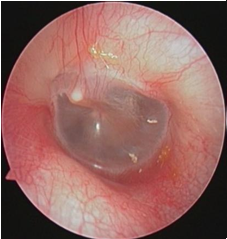

鼓膜是一椭圆形半透明状薄膜,位于中耳鼓室和外耳道之间,是中耳的一道屏障,起到保护中耳和内耳的作用;同时在声音传导过程中起到放大声波作用。

正常鼓膜

中耳炎鼓膜穿孔